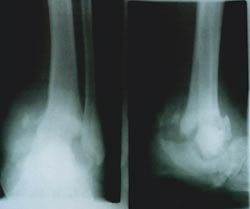

Palpasjon av ekstremitetsarteriene og måling av ankel-arm-indeks med dopplerteknikk inngår i sirkulasjonsutredningen. Ankel-arm-indeksen ligger normalt mellom 0,9 og 1,1. En indeks på < 0,5 tyder på kritisk iskemi. Indeks > 1,2 indikerer mediasklerose. Typiske karforandringer vises også på røntgenbilder. Alternative metoder for å utrede sirkulasjonen i periferien er tåtrykksmåling eller måling av transkutan oksygentensjon (tcpO2). Pasienter med okklusiv karsykdom har signifikant redusert oksygentensjon, og verdien gir derfor også opplysninger om sårprognosen. Dupleksskanning kan påvise stenoser i arteriene. Angiografien er gullstandard for diagnostisering av karforandringer og planlegging av karrekonstruksjon.